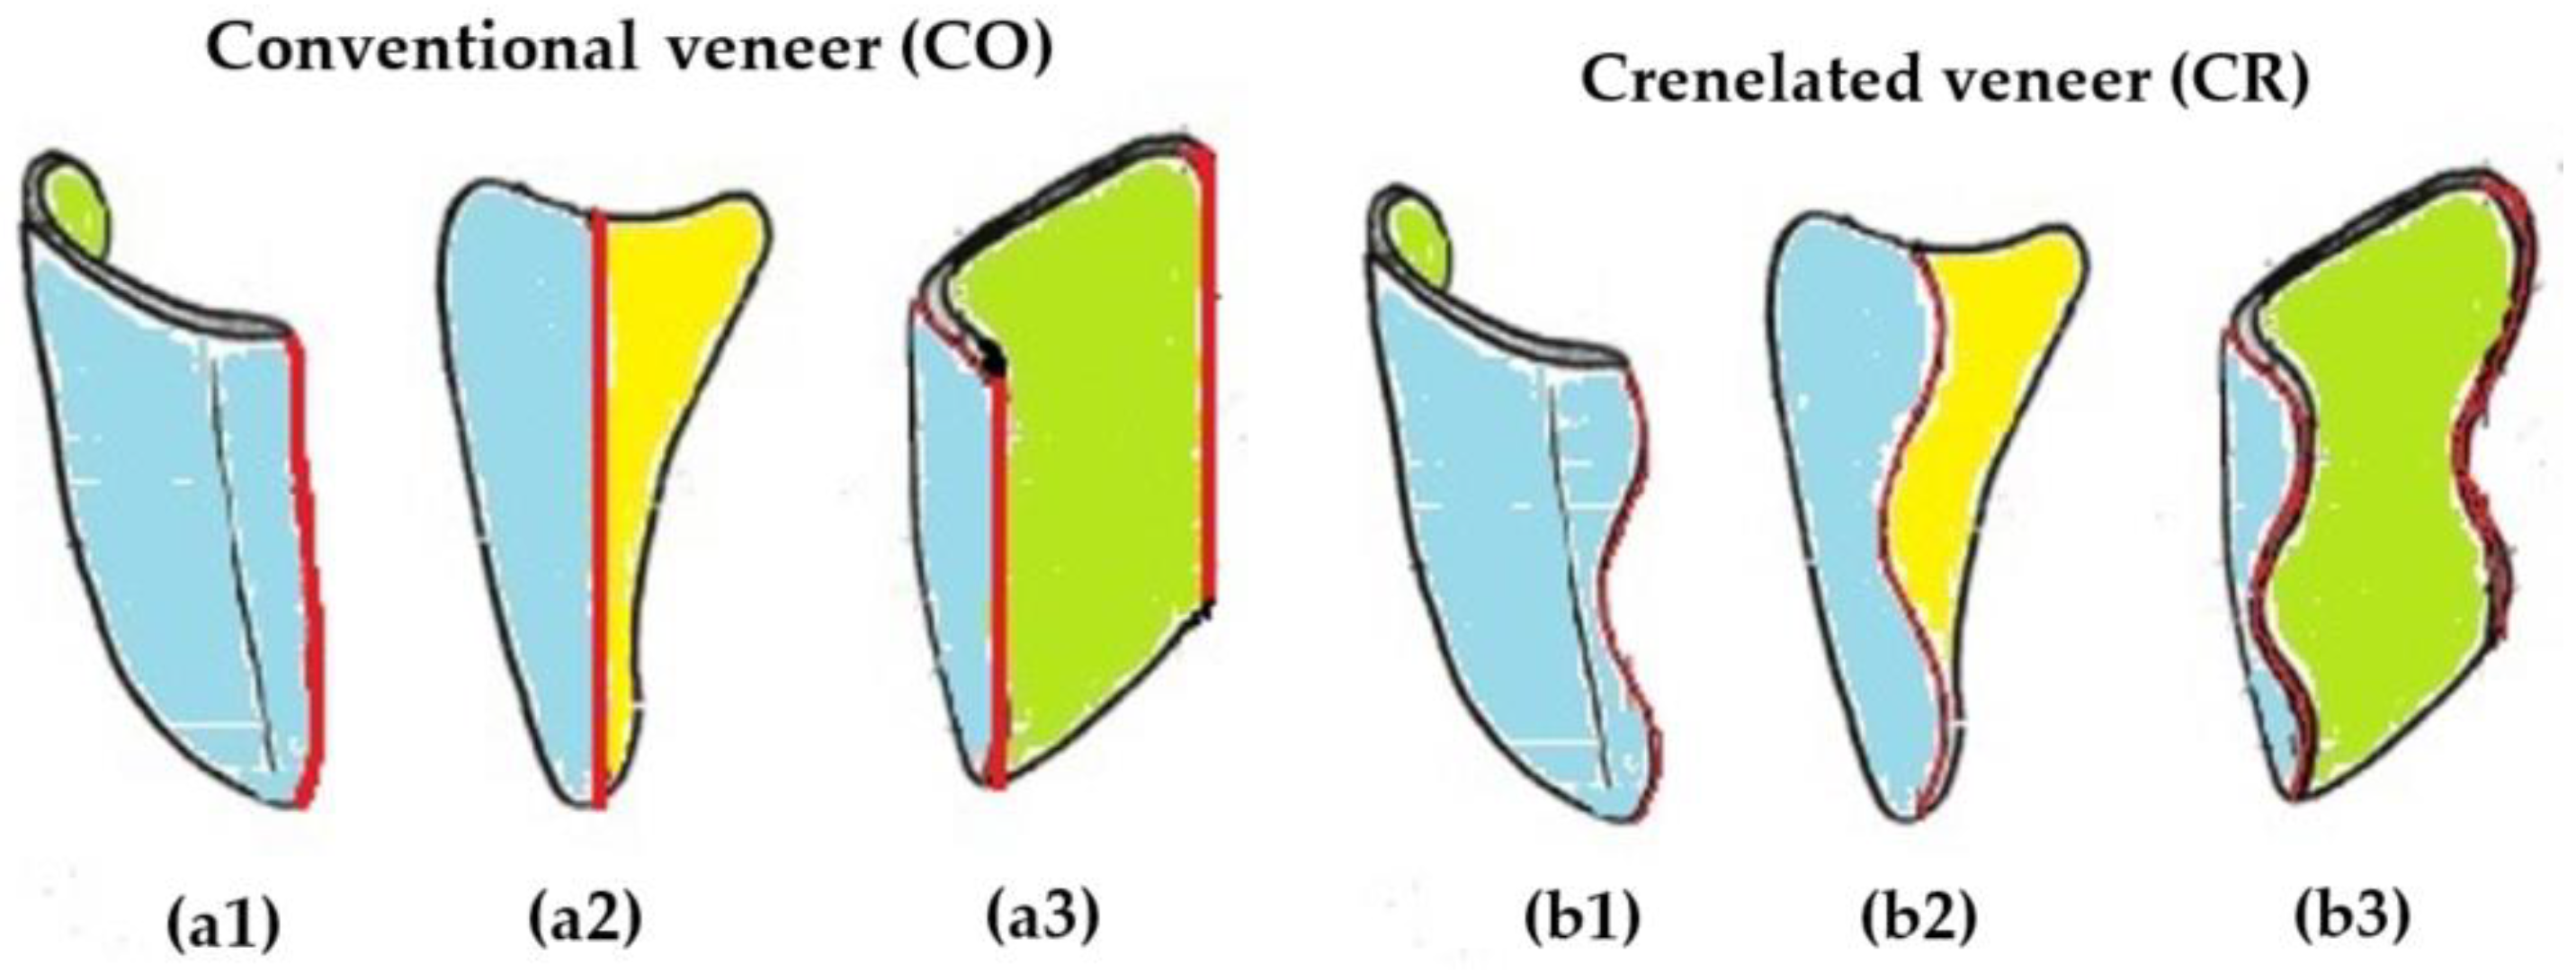

2. Materials and Methods

2.1. Tooth Surface Preparation

2.2. Manufacturing of the Dental Veneers

3.1. Optical Microscopy